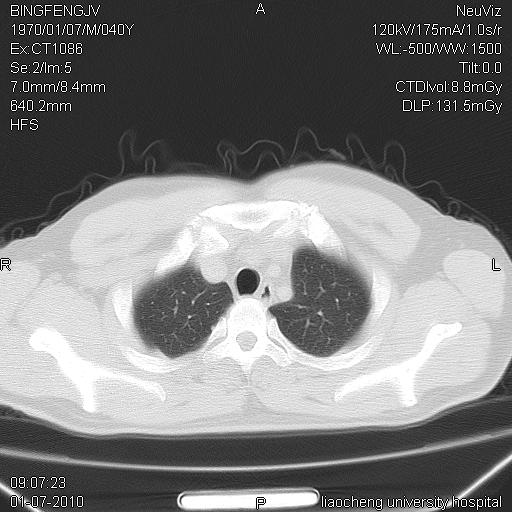

标题: CT23764B:男 40 肺部CT

治疗2周后